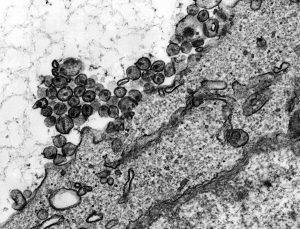

病毒是由遗传物质(DNA或RNA)组成的,这些遗传物质包含在一个表面有蛋白质的保护膜内。为了生存和繁荣,它需要一个宿主——例如,一个人类。一旦宿主被感染,病毒就会利用宿主的细胞机制进行复制。要做到这一点,病毒首先必须结合并进入宿主细胞。病毒遗传物质是一种编码,指示如何合成病毒的每一个成分。在宿主细胞内,数千个包膜蛋白和遗传物质的副本被合成并组装成新的病毒颗粒。然后,这些病毒粒子被释放出来,在宿主体内传播,并感染其他细胞,以保持复制。最后一步是转移到另一个主机。

时不时地,病毒会造成更大的破坏:当两种不同的病毒感染同一细胞时,遗传物质的片段就会发生交换。当它们复制和病毒粒子组装时,全新的重组就产生了:新组装的病毒粒子包含两种病毒的蛋白质。如果这些新病毒能够有效传播,它们就可能成为新的大流行的源头。